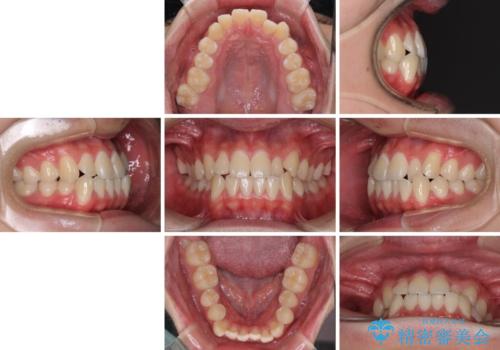

- 前歯のデコボコを治したいとのことで来院された患者様です。

受け口傾向の骨格であり、前歯はクロスバイトまたは切端咬合となっており、叢生は警備であったため、下顎を中心に歯列全体の後方移動を行い、IPR(歯と歯の間を削る)によってデコボコが解消するように設計し、インビザラインにより治療を行うこととしました。

受け口傾向のインビザライン矯正は比較的治療を行いやすいため、きれいに仕上げることができました。舌の突出癖が顕著であったため、改善のためのトレーニングをしっかりと行っていただきました。